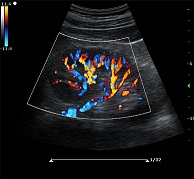

? ? ? ?C7為深圳安盛生物醫(yī)療技術(shù)有限公司新一代便攜式彩超產(chǎn)品,采用了先進(jìn)的PC平臺(tái),擁有強(qiáng)大的處理能力,優(yōu)異的圖像性能,集小巧輕便、全面的功能與輕巧流暢、特有的U型設(shè)計(jì)與一身,提供大眾新選擇。

? ?● 多種成像模式

? ? ? ?B、C、PW、CW、BCD三功、大角度偏轉(zhuǎn)成像、實(shí)時(shí)寬景成像、梯形成像(僅支持線(xiàn)陣)、解剖M型、彩色M型成像、組織多普勒成像、3D/4D成像

? ?● 彩色多普勒增強(qiáng)技術(shù)

? ? ? ?有效抑制彩色血流閃動(dòng)噪聲,提高血流分辨率和靈敏度